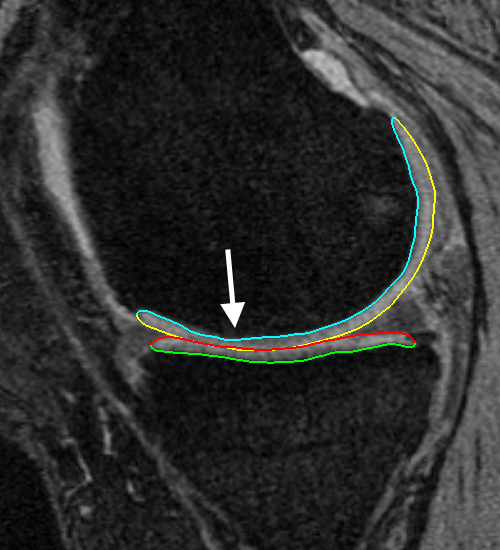

Fig. 3 qualitatively compares the segmentation accuracies between the two methods and the independent standard. Both the femur and tibia are shown with their respective bone and cartilage segmentations showing good agreement between learning-based segmentation and the independent standard.